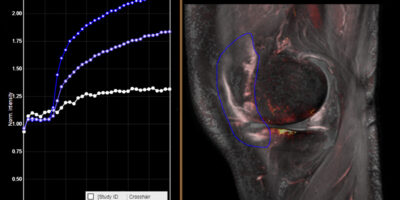

Our award-winning DYNAMIKA platform ensures unparalleled data integrity, while our innovative approach consistently unlocks and amplifies the value of novel therapies.